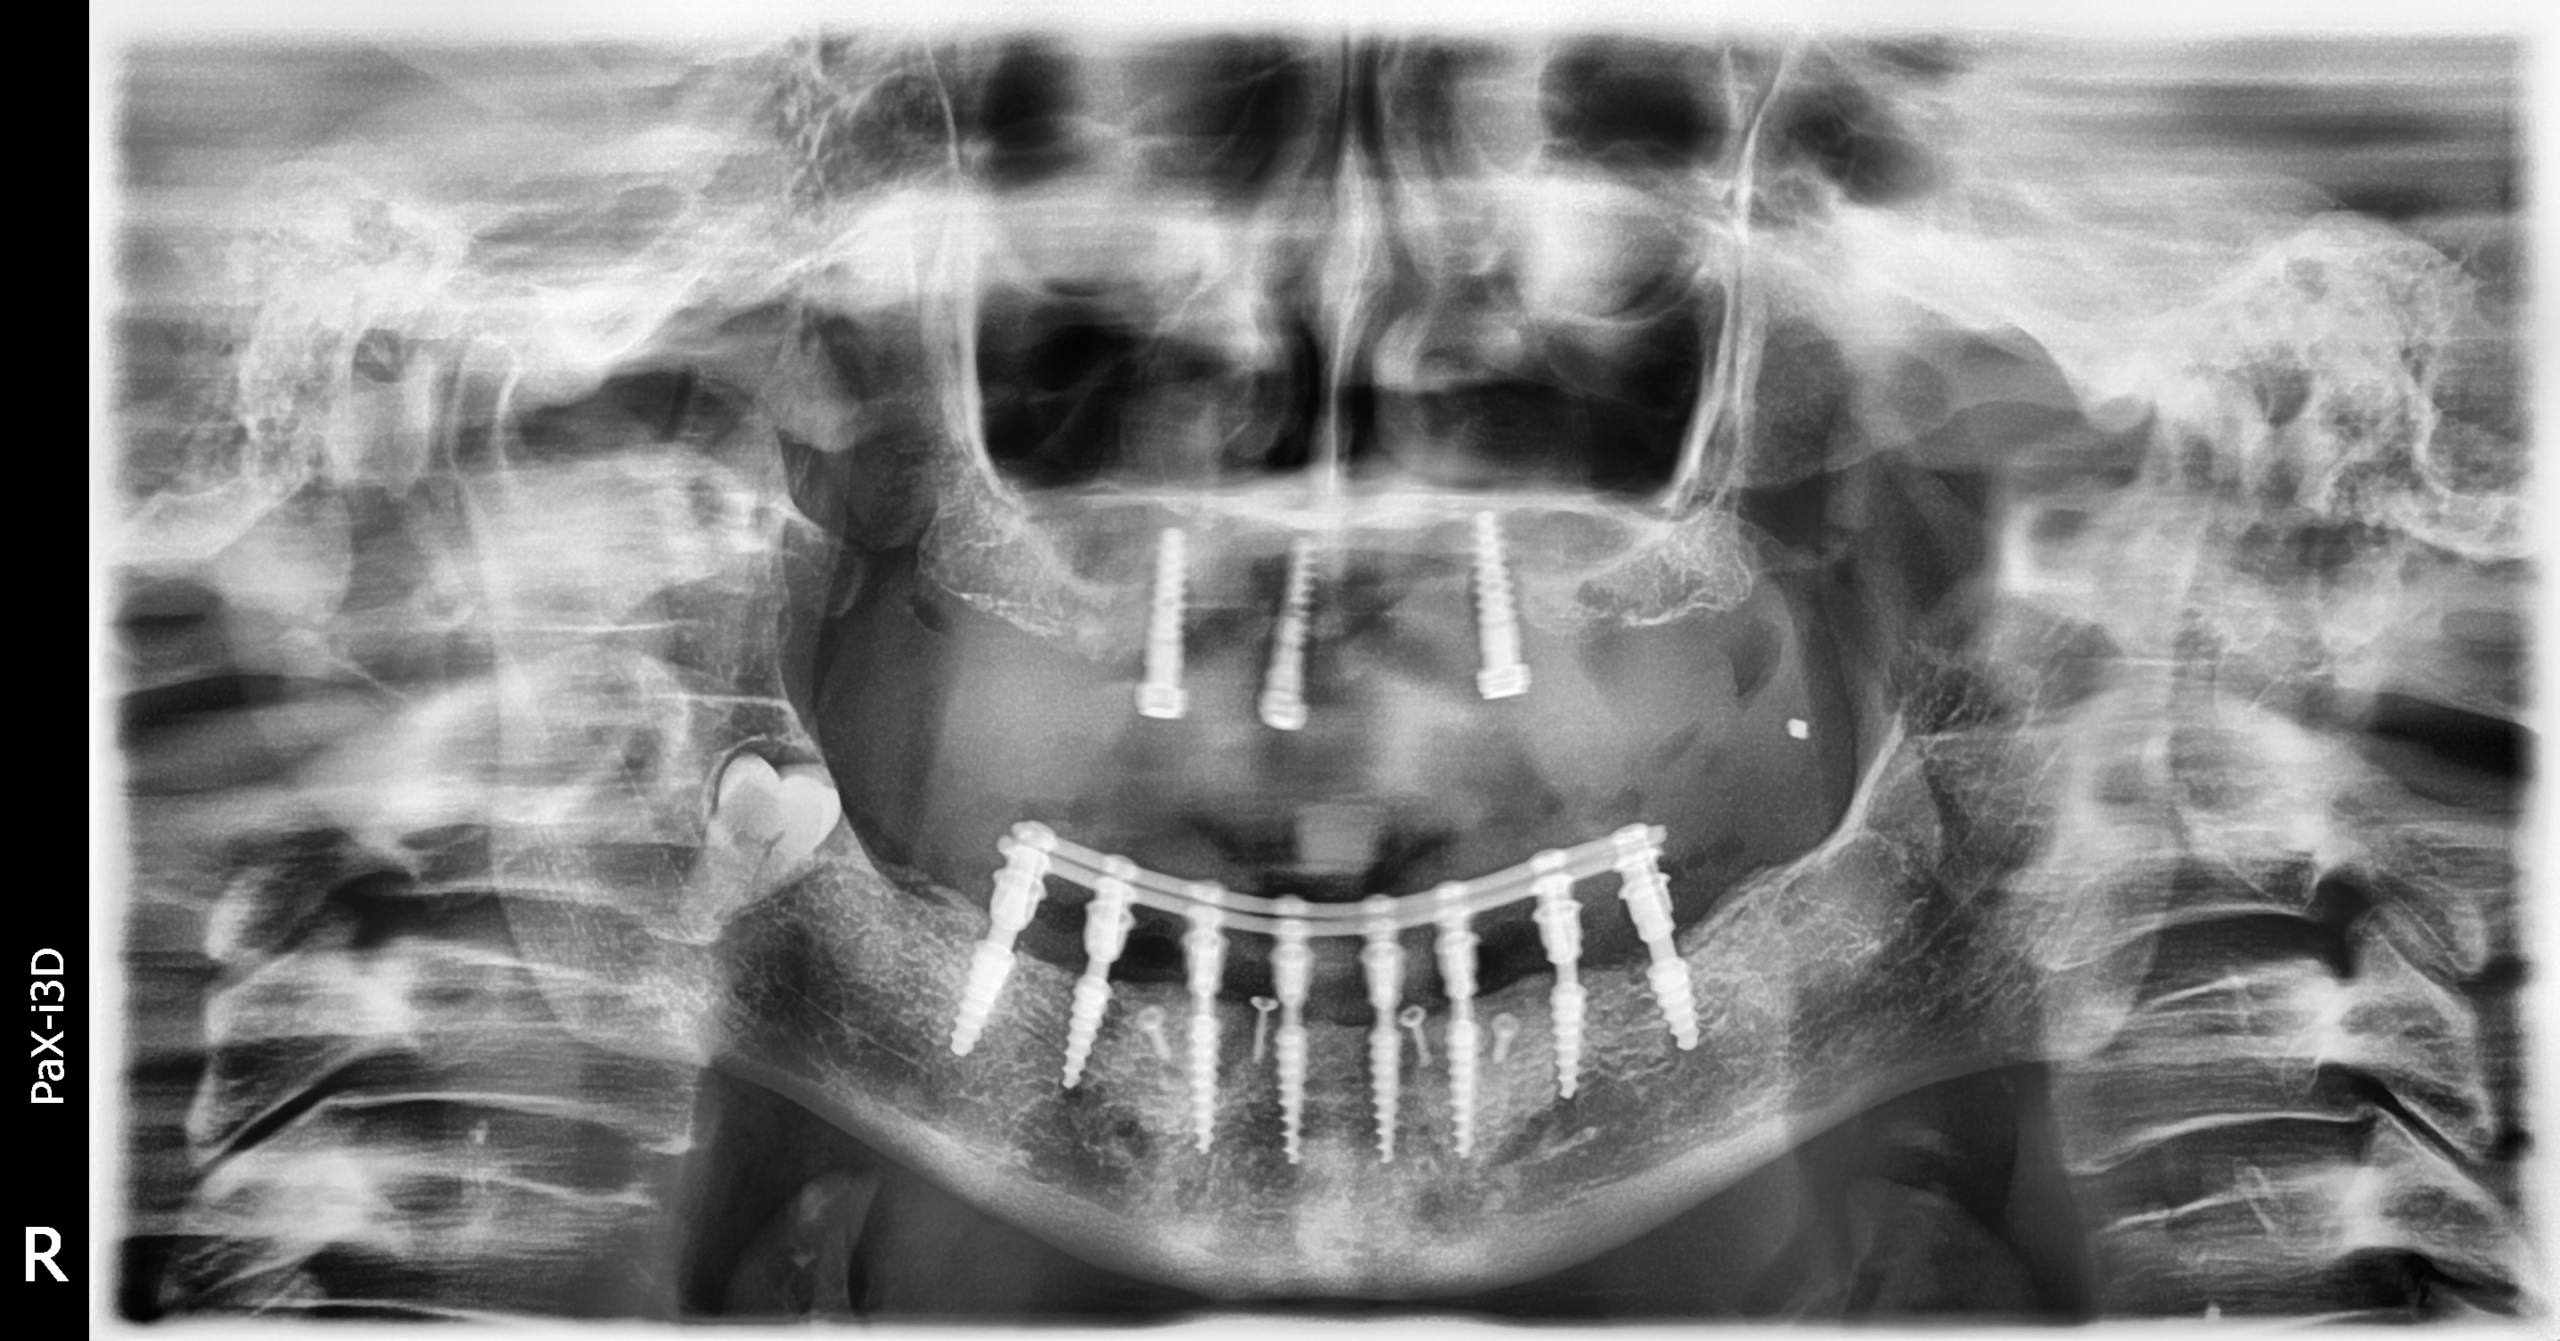

Implantes PCI

Secuencia de imágenes RX, antes y después de la inserción de implantes PCI en la parte superior e inferior de la boca.

Paciente varón de 75 años.

- Radiografía previa a la colocación de implantes Radhex.

- Colocación de implantes Radhex PCI en la parte superior

- Colocación de implantes Radhex PCI en la parte inferior.